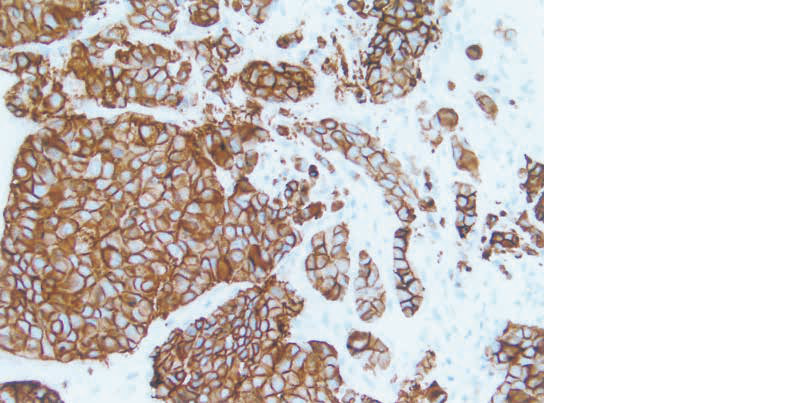

乳癌組織の免疫組織化学染色標本を示す。

使用された抗体はどれか。

• 3. 抗HER2/neu抗体